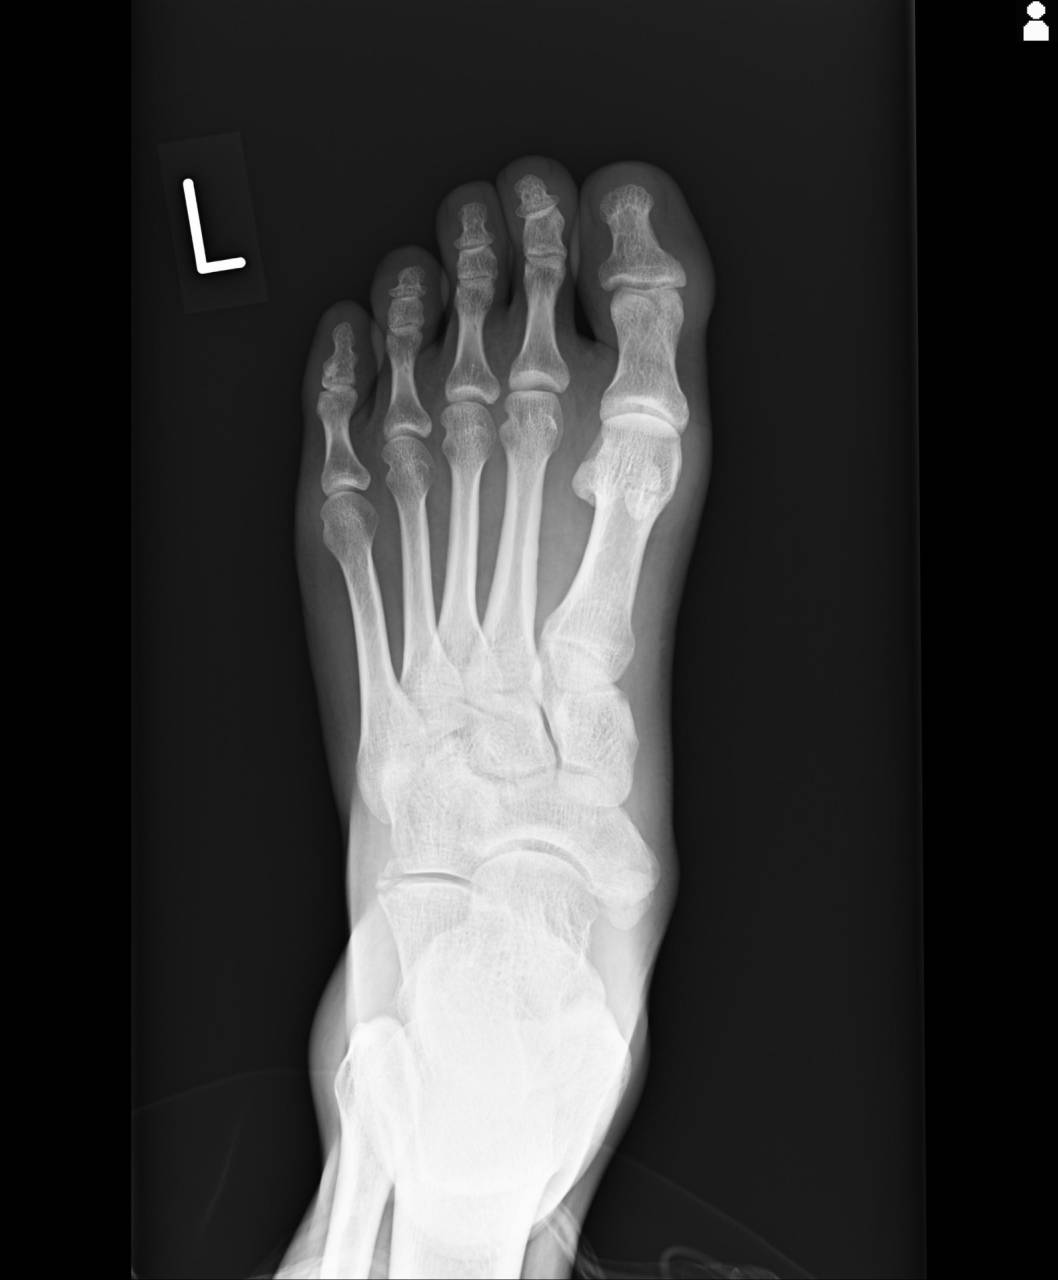

超音波観察装置(エコー)にて確認を行っていくと、左踵骨前方突起に骨折線が確認でき、骨折の疑いがあったため、当整骨院が提携している病院にてレントゲン検査を依頼しました。

撮影した画像を確認すると、踵骨前方突起骨折が確認でき、骨折として施術を行っていきます。